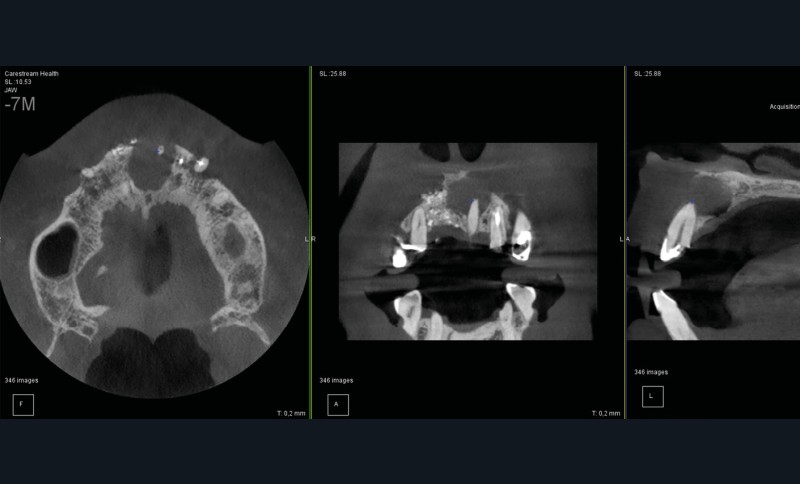

On distingue classiquement le granulome (- 1 cm) du kyste (+ 1 cm). Ce dernier possède des parois propres et des contours réguliers bien délimités. Le développement kystique s’accompagne volontiers d’un refoulement des structures avoisinantes, les corticales osseuses apparaissent soufflées, dans certains cas, amincies, pouvant venir empiéter sur des éléments anatomiques de la sphère maxillo-mandibulaire (sinus, canal mandibulaire, fosses nasales, foramen mentonnier…) (fig. 3).